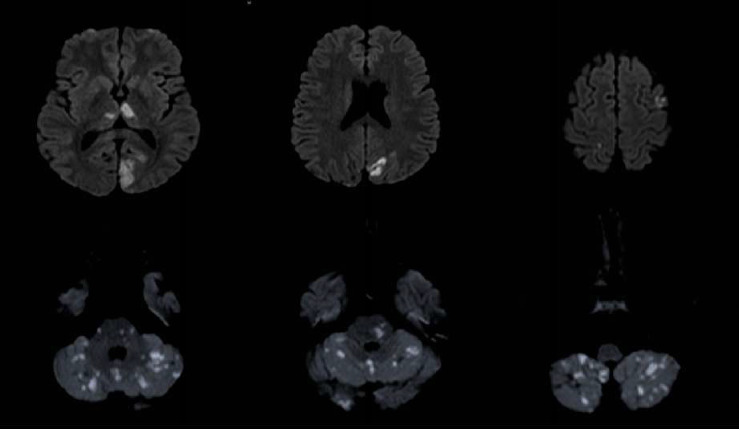

Cardiac myxoma is considered the most common primary cardiac tumor and has been reported to cause different neurological complications through distinctive mechanisms, including pseudovasculitis. Herein, we present and review a case of a young male with a previous history of ischemic stroke who presented with multiple territorial ischemic insults in the presence of a presumed diagnosis of vasculitis. Once further workup was done, he was found to have a left atrial myxoma.